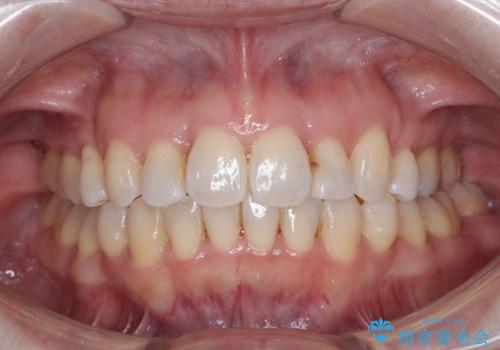

飛び出した上顎前歯と上下のデコボコ 片顎の抜歯によるワイヤー矯正

- 上下前歯のデコボコと、上顎の八重歯を気にして来院された患者様です。

下顎に対して上顎が前方にあり、第一大臼歯による咬合状態は上顎前突であったため、上顎のみ左右の第一小臼歯を抜歯し、ワイヤー装置にて矯正治療を行うこととしました。